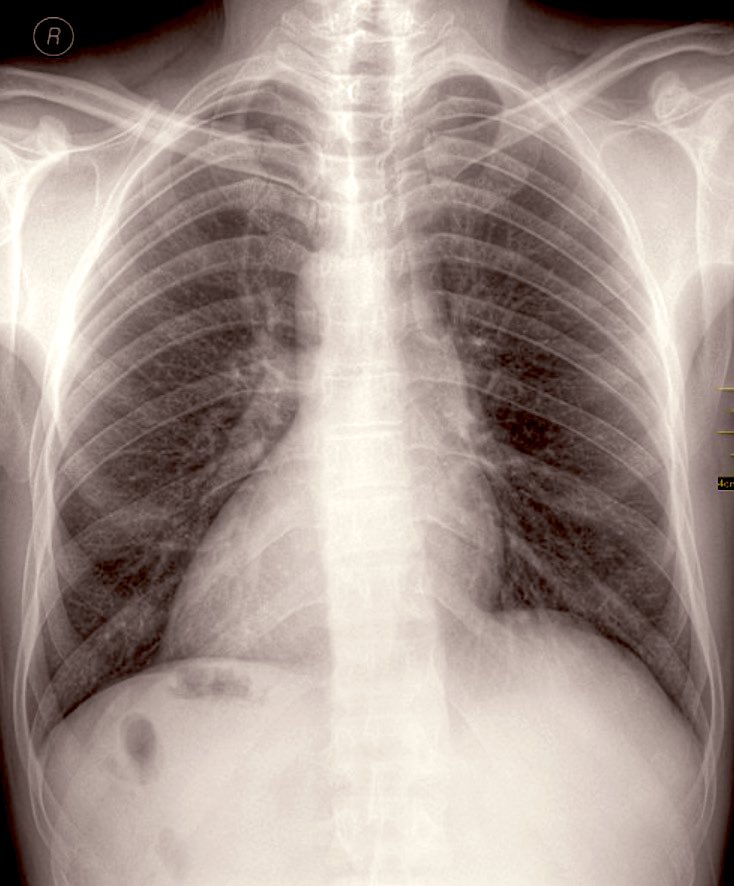

Kalp soldadır çünkü solda olması yaşamın mümkün olmasının koşuludur — hem biyolojik hem fenomenolojik anlamda. Şimdi soru şu? Resime bakın..

Kalbiniz solda mı?